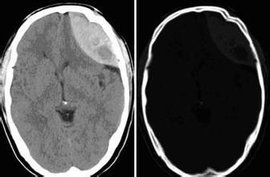

硬腦膜下血腫是指出血積聚於硬腦膜下腔是顱內血腫中最常見者常呈多發性或與別種血腫合併發生。

硬膜下血腫是常見的顱內血腫之一,可分為急性,亞急性及慢性三種。